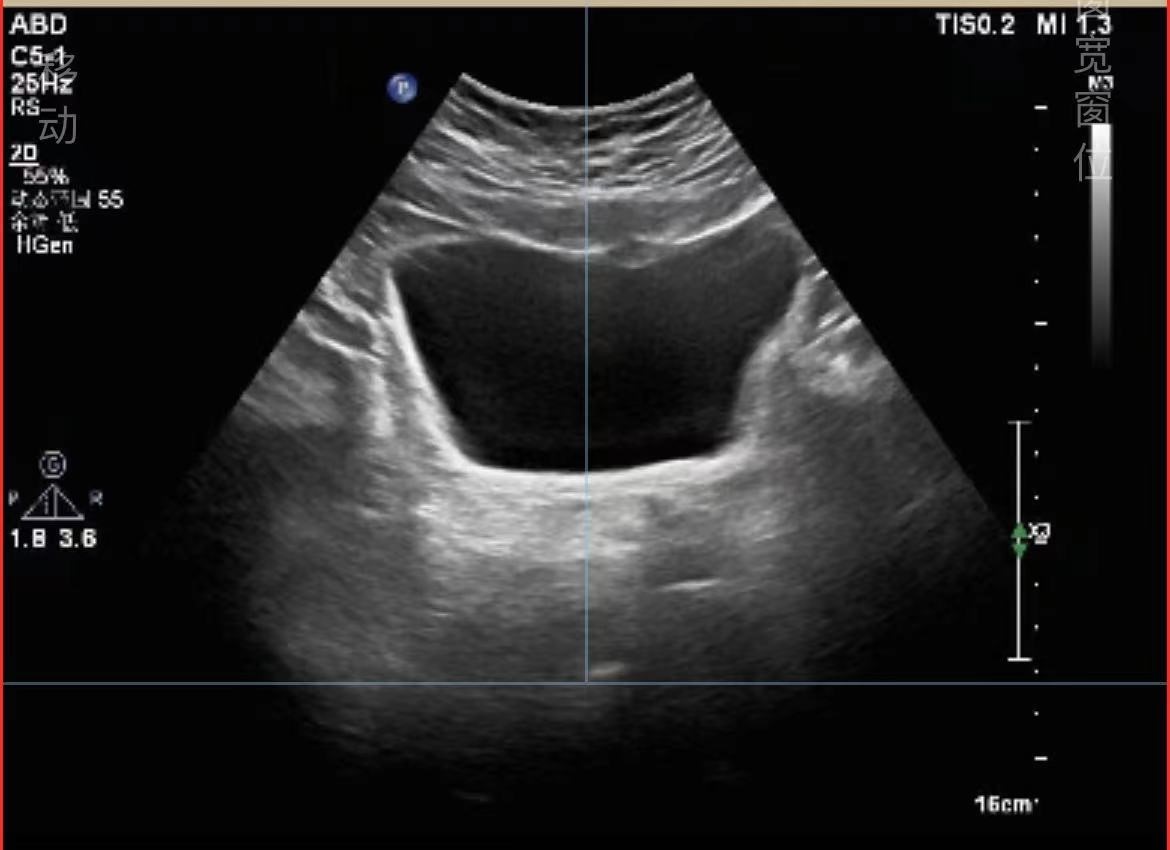

那具体怎么做呢?通过记录排尿过程中的曲线,就可以推算出排尿功能情况了。而且只需要进行一次简单的排尿,就可以得到多项数值如最大尿流率、排尿时间、排尿量等等。此外,在排完小便后行超声检查膀胱内残余液体量也能间接反映膀胱功能是否正常。